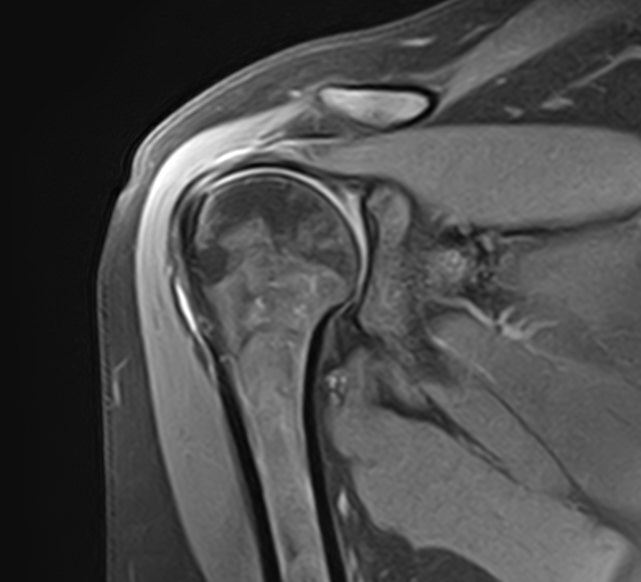

Магнитно-резонансная томография является современным высокоточным методом диагностики заболеваний опорно-двигательной системы человека. Во время исследования аппарат послойно сканирует анатомическую зону в различных плоскостях, затем с помощью компьютерных программ формирует трехмерные изображения с высокой точностью и достоверностью, что позволяет проводить эффективную диагностику заболеваний суставов.

Для выявления причин множественного поражения суставов в клинике «Доступная медицина» проводится комплексное обследование МРТ двух суставов, включающее два протокола исследования каждой анатомической области. При одностороннем поражении сустава также может назначаться МР сканирование одновременно двух симметричных сочленений для сравнения пораженной области со здоровым суставом на противоположной стороне. Это позволяет проводить более эффективную диагностику заболеваний суставов и назначать успешное лечение.

Какую патологию суставов можно выявить с помощью МРТ

• Из-за интенсивных нагрузок суставы часто подвержены травматизации (вывихи, подвывихи, внутрисуставные переломы, кровоизлияния в полости суставов – гемартрозы, растяжения, разрывы связок и сухожилий, ушибы мягких тканей),

• Воспалительные заболевания суставов (артриты, бурситы, синовиты, тендиниты, тендовагиниты).

• Дегенеративно-дистрофические заболевания суставов (артрозы, остеоартрозы).

• Врожденные аномалии развития (дисплазии, различные деформации и др).

• Выявление доброкачественных новообразований, например, кист и злокачественных опухолей (как первичных, так и метастазов).

• Обнаружение сосудистых заболеваний, поражений нервных волокон, патологии окружающих сустав мягких тканей.